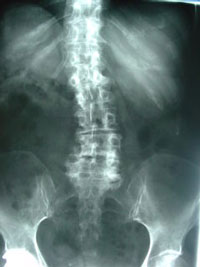

Well, that is not completely factual. Old Mill Chiropractic treats many St Peters seasoned patients with scoliosis and helps calm their pain with chiropractic. Scoliosis (a curvature of the spine) can develop in the early years of life and then decline OR bring about disc degeneration and pinched nerves in the middle back and lower back. The pinched nerves are formed by a condition called spinal stenosis (a narrowing of the nerve opening spaces in the spine). Now, the condition of scoliosis and disc degeneration may cause pain in the legs due to stenosis. Pain down the legs called sciatica is caused by a specific pinched nerve. But chiropractic can help!

Spinal stenosis in older adults with scoliosis is commonplace in our chiropractic, so you’re not by yourself! As a matter of fact, one study of 36 patients with a mean age of 69 years had leg pain at a severity level of 6.5 (on a scale of 0 no pain to 10 the worst pain the patient had ever had). 97% of these patients also showed at least one level of severe stenosis, and all but one had severe leg pain, too. (1) Your St Peters chiropractor at Old Mill Chiropractic is trained and ready to advise you on an effective stenosis and scoliosis treatment plan to gain pain relief.